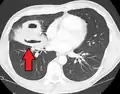

Computed tomography (CT) scan of chest showing bilateral pneumonia with abscesses, effusions, and caverns. 37-year-old male.